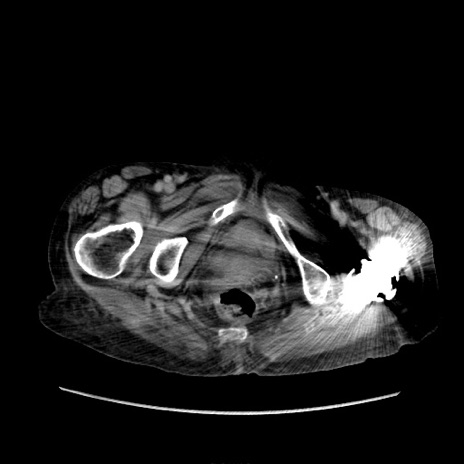

矢状断像

【症例】80歳代 女性

【主訴】腹部膨満感

【現病歴】他院にて肝硬変にてフォロー中。1週間前から便秘、腹部膨満感、臍部腫瘤あり受診となる。

【既往歴】肝硬変

【身体所見】腹部膨隆あり、皮膚変化なし、疼痛なし。

【データ】WBC 4600、CRP 0.25